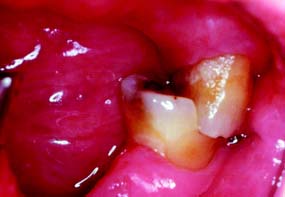

One of the basic tenets of restorative dentistry is to conserve as much tooth structure as possible while preparation design remains consistent with the mechanical and esthetic principles of tooth preparation. Tissue preservation reduces the harmful pulpal effects of the various procedures and materials used. The thickness of remaining dentin has been shown21 to be inversely proportional to the pulpal response, and tooth preparations extending in close proximity to the pulp should be avoided. Dowden22 argued that any damage to the odontoblastic processes would adversely affect the cell nucleus at the dentin-pulp interface, no matter how far from the nucleus it occurred. For this reason, in the assessment of likely adverse pulpal response, the amount of removed dentin is important; particular care must be exercised when vital teeth are prepared for complete-coverage restorations (Fig. 7-8).

Fig. 7-8 A considerable amount of care is needed when a tooth is prepared for a complete crown, because of the extensive nature of the reduction, with many dentinal tubules sectioned. Each tubule communicates directly with the dental pulp.